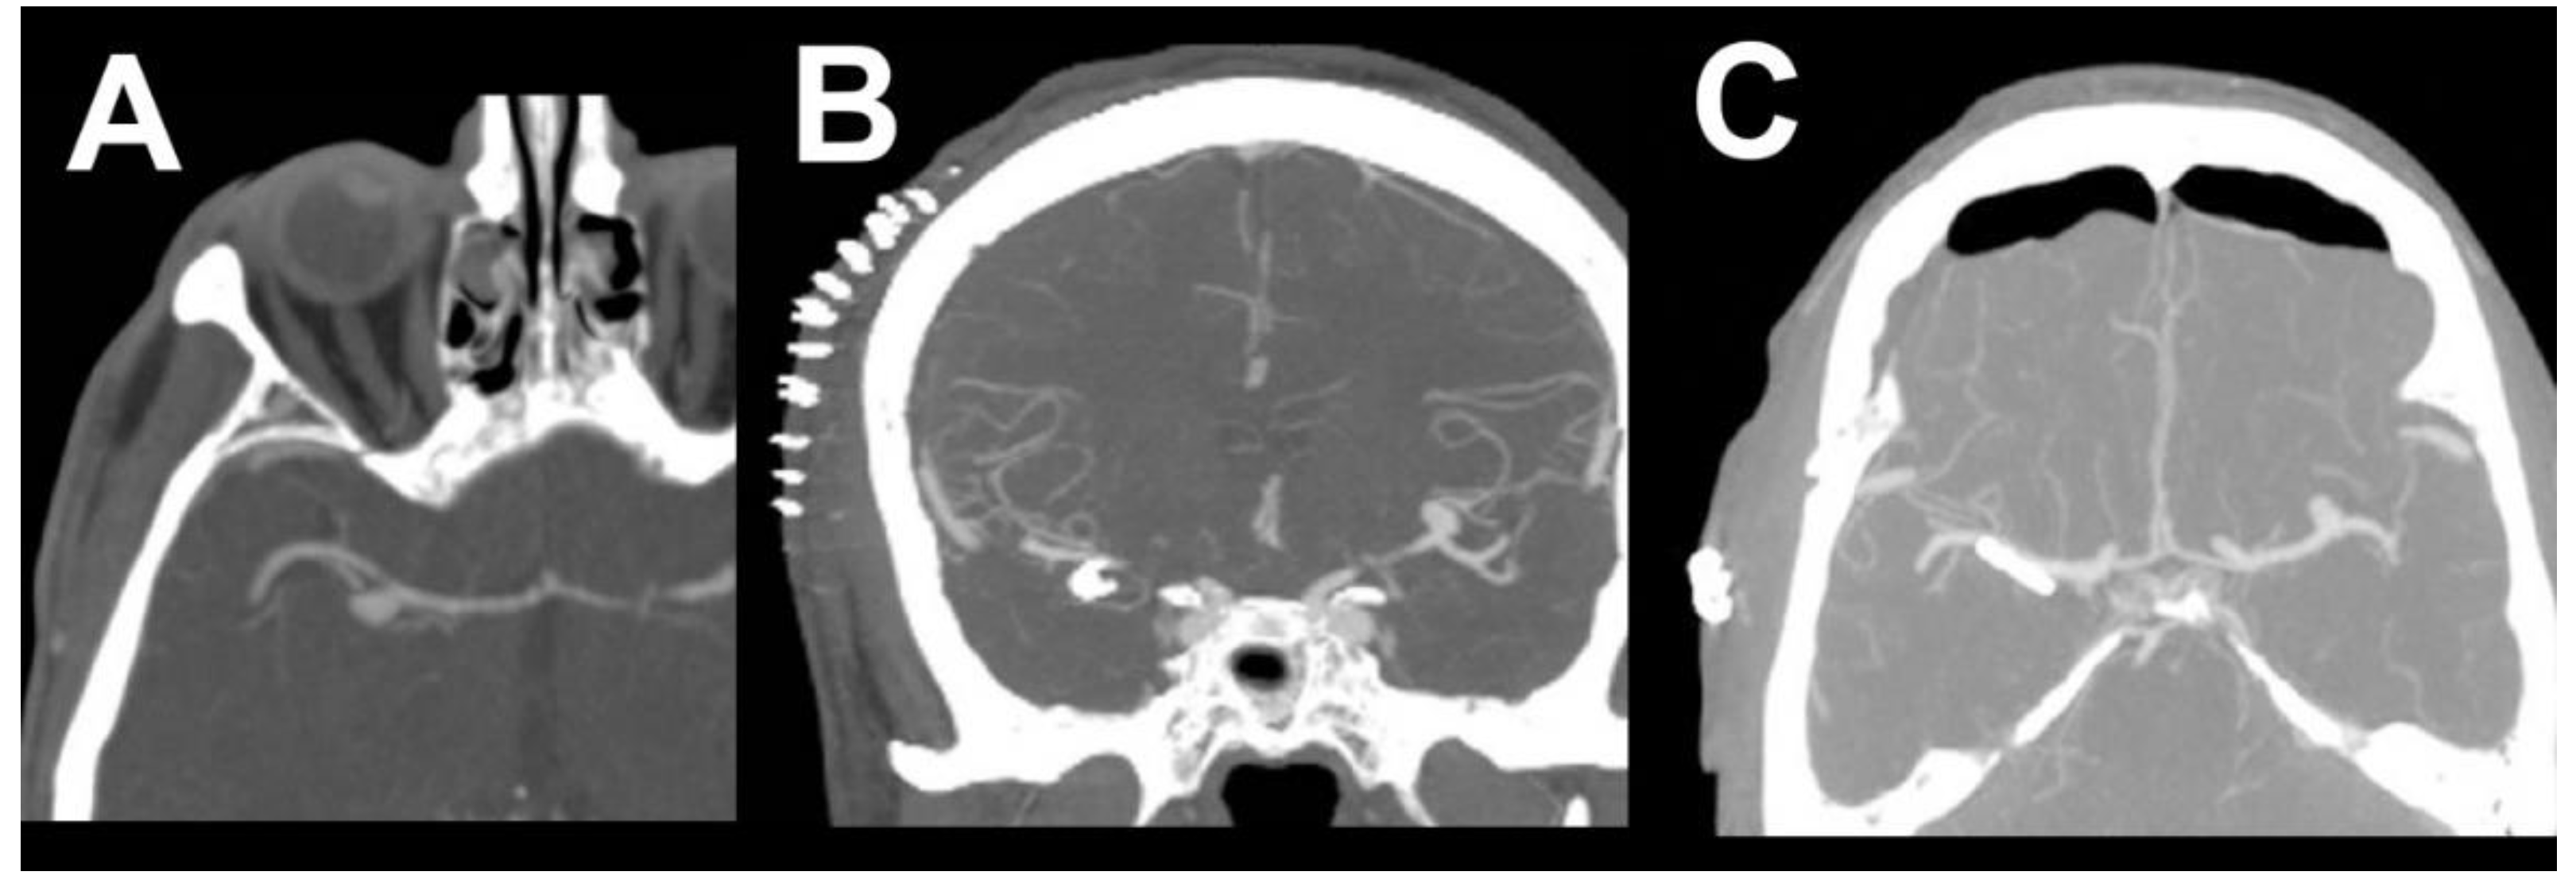

2. Case Report 1

3. Case Report 2